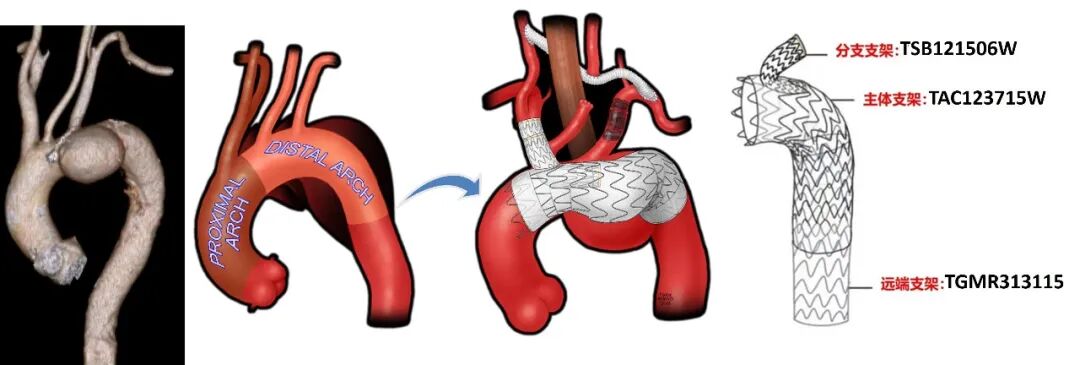

行右颈动脉-左颈动脉-左锁骨下动脉搭桥术,植入GORE® TAG® 分支型胸主动脉覆膜支架(以下简称“TBE”),TBE主体支架锚定于Zone 0,重建无名动脉血运,左锁骨下动脉栓塞。支架型号:主体支架TAC123715W+分支支架TSB121506W,远端可主动调控胸主动脉覆膜支架TGMR313115。

斑马导丝是治疗什么的「胸有乾坤」至简至易 行之有效—— Zone 0 TBE植入治疗弓部动脉瘤病例报道_https://www.jmylbn.com_新闻资讯_第12张

手术示意图